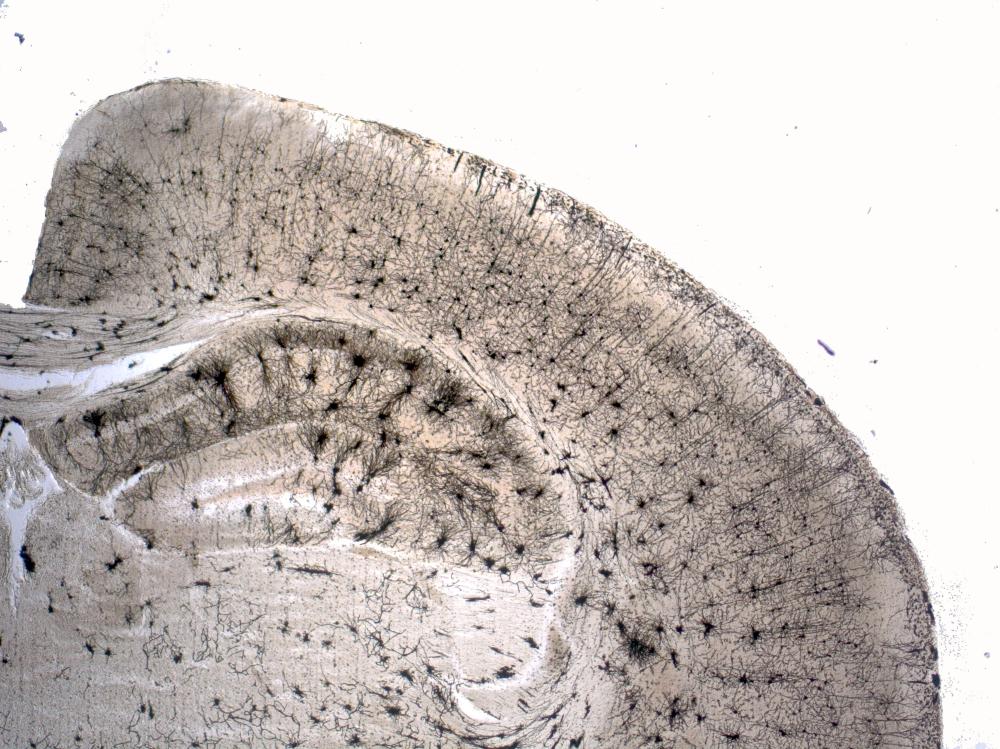

Neurodegenerative diseases are characterized by a progressive loss of structure and function of neurons in the central nervous system ultimately resulting in cell death. Common neurodegenerative diseases include Alzheimer’s disease (AD), Parkinson’s disease (PD), amyotrophic lateral sclerosis (ALS), and multiple sclerosis (MS). To date, no treatment is available to halt or reverse the underlying disease progression and clinical diagnosis is still challenging often only definite after autopsy.

The Trønderbrain project aims to understand molecular processes that drive the initiation and progression of neurodegenerative diseases with special emphasis on AD. The overall goal is to identify novel biomarkers for early diagnosis and targets for effective therapy.